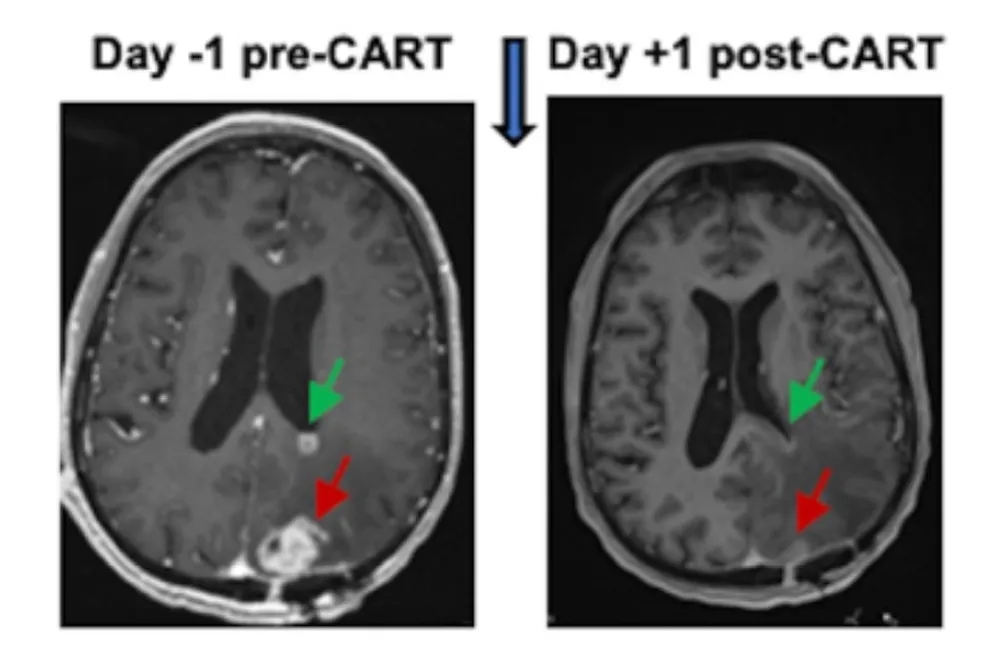

在1期试验(NCT05168423)中,纳入6例复发性胶质母细胞瘤患者,采用鞘内注射的方式,对患者施用这款“EGFR”和“IL13Rα2”双靶点CAR-T细胞(即CART-EGFR-IL13Rα2)后,24~48小时复查MRI显示,所有6例患者的肿瘤体积均缩小(详见下图),而且部分患者缩小状态维持数月。此外,神经毒性也在可控范围内。

图1 一例胶质母细胞瘤患者治疗前后MRI变化

▲图源“Penn Medicine News”,版权归原作者所有,如无意中侵犯了知识产权,请联系我们删除